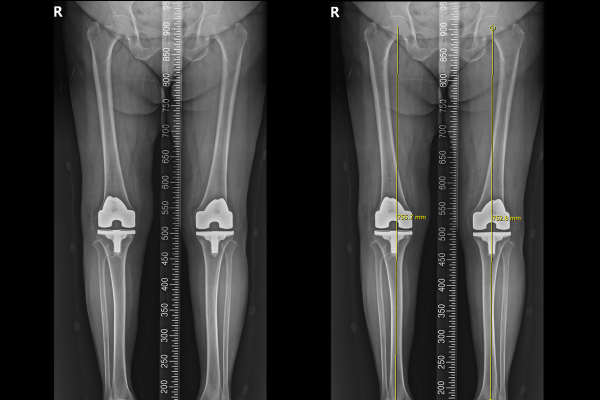

환자분의 무릎 상태를 확인하기 위해 X-RAY를 촬영하였을 때, 다리 정렬이 맞지 않는 것이 확인 됩니다.

6c762d0732f22ffa67d913492363433d_1766047120_4903.png

반치환술을 시행한 우측 무릎을 자세히 보면 내측 공간이 평소보다 많이 좁아져 있는 것이 확인되는데, 이는 폴리에틸렌으로 제작된 인공관절의 마찰면, 인공 물렁뼈(인공 연골판)의 손상이 의심되는 상황으로, 우측 무릎 인공관절 인공연골판 파절[손상](Rt. Knee insert breakage of previous UKA)을 진단하였습니다.